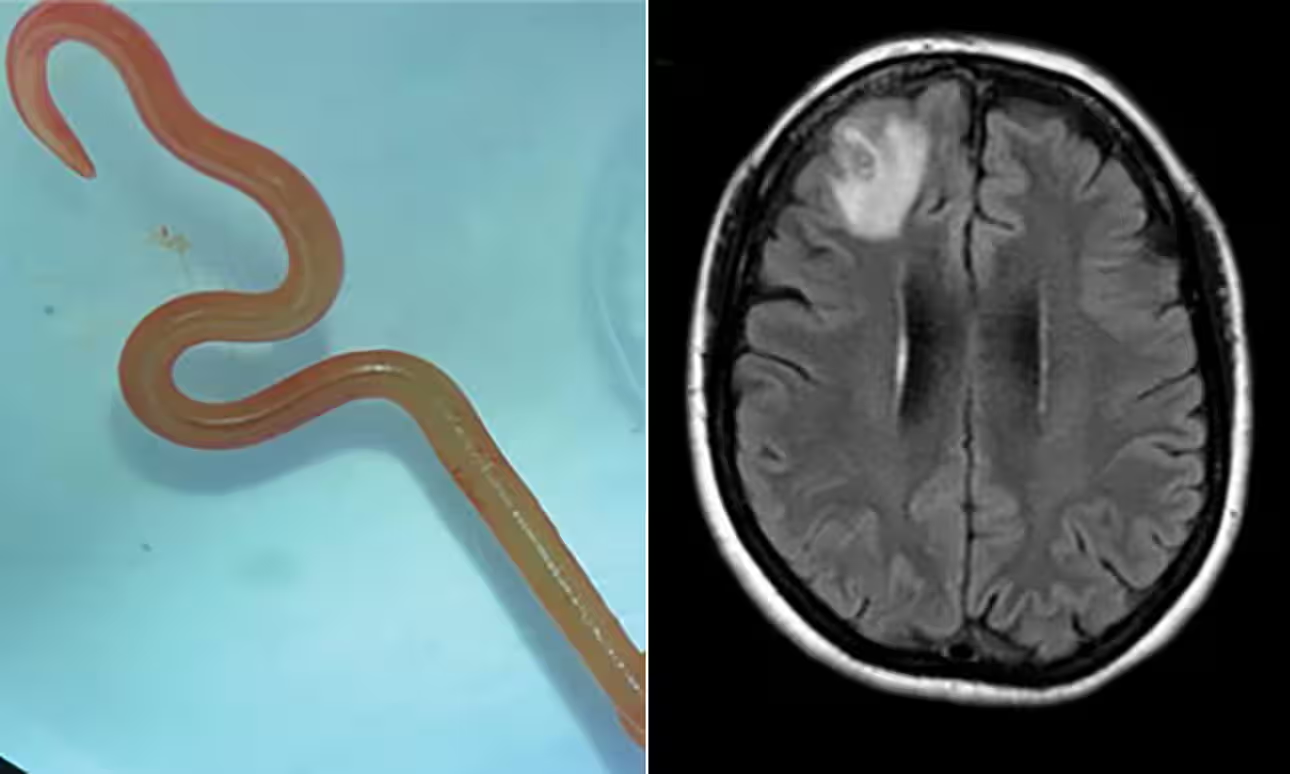

CANBERRA: Memetik laporan bernama menerusi Harian Metro, cacing gelang Ophidascaris Robertsi yang masih hidup berukuran lapan sentimeter itu yang biasanya ditemukan di dalam ular sawa, dikeluarkan daripada otak pesakit wanita berusia 64 tahun selepas pembedahan.

Selepas pesakit itu mula mengalami kealpaan dan kemurungan pada 2022, seorang pakar bedah saraf di Hospital Canberra mengenal pasti kelainan pada lobus hadapan kanan otaknya melalui imbasan pengimejan Resonans Magnetik (mri).